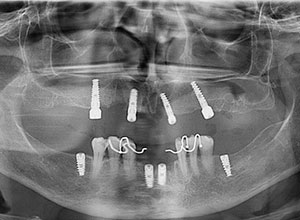

Este procedimiento requiere, en primer lugar, que tomemos los registros de la boca del paciente a través de una tomografía cone beam la cual se transfiere a el software que se encarga de proyectar la prótesis a través de la reproducción digital en 3D y obtener el mejor diagnóstico.

En el mismo software se realiza la planificación para la colocación de los implantes colocando virtualmente los implantes en la zona favorable y de esta manera se realiza una guía quirúrgica.

El día de la cirugía la paciente sale de la clínica con prótesis inmediatas removibles las cuales fueron elaboradas con modelos de trabajo tomados previo a la cirugía.